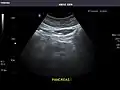

Pancreas

Pancreas: Visualized portions unremarkable.